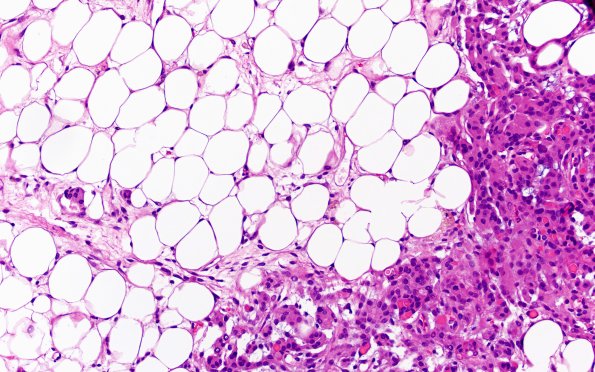

17C3 Meningioma, lipidized (Case 17) 10X

There is extensive lipidization of tumor cells as well as presence of secretory material. (H&E)